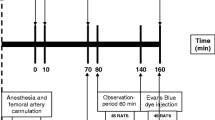

Perioperative tissue hypoperfusion may result in postoperative complications and increased mortality1. The common causes of perioperative hypoperfusion are general anesthesia-induced hypotension, blood loss, and fluid loss. Intraoperative administration of crystalloids is commonly used to treat perioperative hypoperfusion. However, research has proved that fluid loading has no influence on anesthesia-induced hypotension2, and excessive fluid supplementation may cause hypervolemia-related glycocalyx impairment3, tissue edema, respiratory distress syndrome4, and abdominal compartment syndrome5. Postoperative fluid overload has been demonstrated to be strongly correlated with mortality6. Several studies have shown that vasopressors may be more appropriate for treating anesthesia-induced hypotension and prevent hypervolemia7,8. Furthermore, microcirculatory dysfunction can occur in the absence of arterial hypotension9,10,11,12. Intestinal microcirculatory dysfunction can lead to the disruption of the intestinal mucosal barrier and the development of multiple organ dysfunction syndrome13. To the best of our knowledge, no study has compared the treatment effects of fluid supplementation and vasopressor infusion on intestinal microcirculation. The primary aim of this study was to compare the treatment effects of fluid supplementation and vasopressor infusion on intestinal microcirculation during intraoperative anesthesia-related hypotension in an open abdominal surgery rat model (Fig. 1).

The 32 rats were randomly assigned to four groups (8 rats in each group) (Fig. 1). In the LA group, the rats received 0.8–1% (the inspiratory concentration) isoflurane inhalation, with a continuous infusion of 0.9% sodium chloride at 2 mL/kg/h as the maintenance fluid supplementation through an external jugular vein catheter. In the DA group, the rats received 1.5–1.8% isoflurane inhalation with a continuous infusion of 0.9% sodium chloride at 2 mL/kg/h. In the Fluid DA group, rats receiving 1.5–1.8% isoflurane inhalation with a continuous infusion of 0.9% sodium chloride, and the infusion rate was adjusted to maintain MAP decreased by less than 10 mm Hg of the initial value. The rats were given a 1 mL bolus of 0.9% sodium chloride for persistent hypotension. In the Norepinephrine DA group, rats received 1.5%-1.8% isoflurane inhalation with a continuous intravenous infusion of norepinephrine (60 mcg/mL in 5% dextrose), and the infusion rate was adjusted to maintain MAP decreased by less than 10 mmHg of the initial value. Subsequently, they were administered a bolus of 1 mL of 0.9% sodium chloride for persistent hypotension. The infusion concentration of norepinephrine was determined by our pilot study.